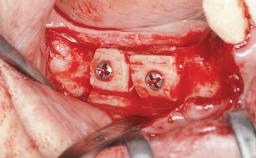

A 20-year-old woman was referred for implant therapy in 2004. Her medical history revealed no significant findings, and neither did she smoke nor take any medications. An extraoral examination revealed no abnormalities of the skin, hair or nails. The intraoral examination revealed only 11 permanent teeth clinically. These were normal in shape, size, and color. In addition, eight retained deciduous teeth (53, 62, 63, 71, 72, 73, 81, 82) were present. No abnormalities were detected during the general examination. The family history revealed that the patient’s father and two sisters were on record with similar conditions. The clinical examination revealed a thick gingival biotype. No recession of the attached gingiva was noted, but the retained deciduous teeth were mobile and unsightly. As a syndrome had not been diagnosed, the case was categorized as non-syndromic oligodontia.

Bone Augmentation Horizontal|Staged

Augmentation Materials Autogenous chips|Autogenous block(s)|Membrane

Bone Volume Deficient horizontally, requiring prior grafting